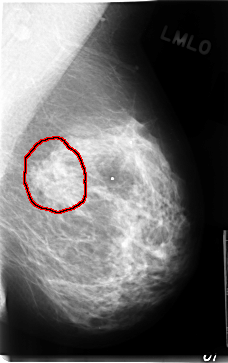

C_0080_1.LEFT_MLO

FILE: C_0080_1.LEFT_MLO.OVERLAY

TOTAL_ABNORMALITIES 1

ABNORMALITY 1

LESION_TYPE MASS SHAPE IRREGULAR MARGINS ILL_DEFINED

ASSESSMENT 4

SUBTLETY 2

PATHOLOGY MALIGNANT

TOTAL_OUTLINES 1

BOUNDARY